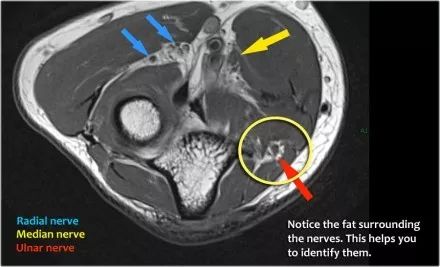

桡神经:在桡骨头水平可以最好地识别桡神经,在那里你可以看到桡骨隧道中的浅表和深支(箭头)。这是寻找桡神经的非常一致的地方。

深分支形成后骨间神经,穿过Frohse拱门(箭头)的旋后肌。

中位神经:正中神经落后于Lacertus纤维,即肱二头肌的腱膜并穿透旋前肌。